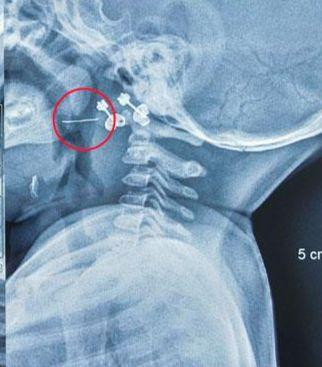

Tại Bệnh viện Nhi Trung ương, sau khi trẻ được thăm khám, soi họng và đọc kết quả phim X-Quang, các bác sĩ xác định có dị vật kim loại đâm xuyên qua Amidan bên trái của trẻ. Bác sĩ Nguyễn Khắc Trưởng, khoa Tai – Mũi – Họng, Bệnh viện Nhi Trung ương, người trực tiếp gắp dị vật cho bệnh nhi cho biết “Nhận thấy dị vật mắc ở vị trí phức tạp, nguy cơ chảy máu cao, chúng tôi đã nhanh chóng cho trẻ làm các xét nghiệm cần thiết rồi chuyển lên phòng mổ, gây mê và tiến hành gắp dị vật lấy ra được sợi thép nhỏ nhưng rất cứng và nhọn 2 đầu, dài 2cm.”

| Hình chụp sợi thép xuyên qua Amidan trái của trẻ |

Sợi thép này đâm xuyên từ cực trên xuống cực dưới Amidan bên trái của trẻ. May mắn là dị vật chưa xuống sâu hơn nên không gây nguy hiểm đến tính mạng của trẻ. Nếu không được gắp ra kịp thời, đoạn kim loại này có thể gây nhiễm trùng và chảy máu, dẫn đến những hậu quả khó lường. Dị vật nguy hiểm nói trên được xác định là rơi ra từ rây lưới thép để lọc đồ ăn, bị lẫn vào cháo của trẻ trong quá trình chế biến. Hiện tại tình trạng của trẻ đã ổn định và được xuất viện.